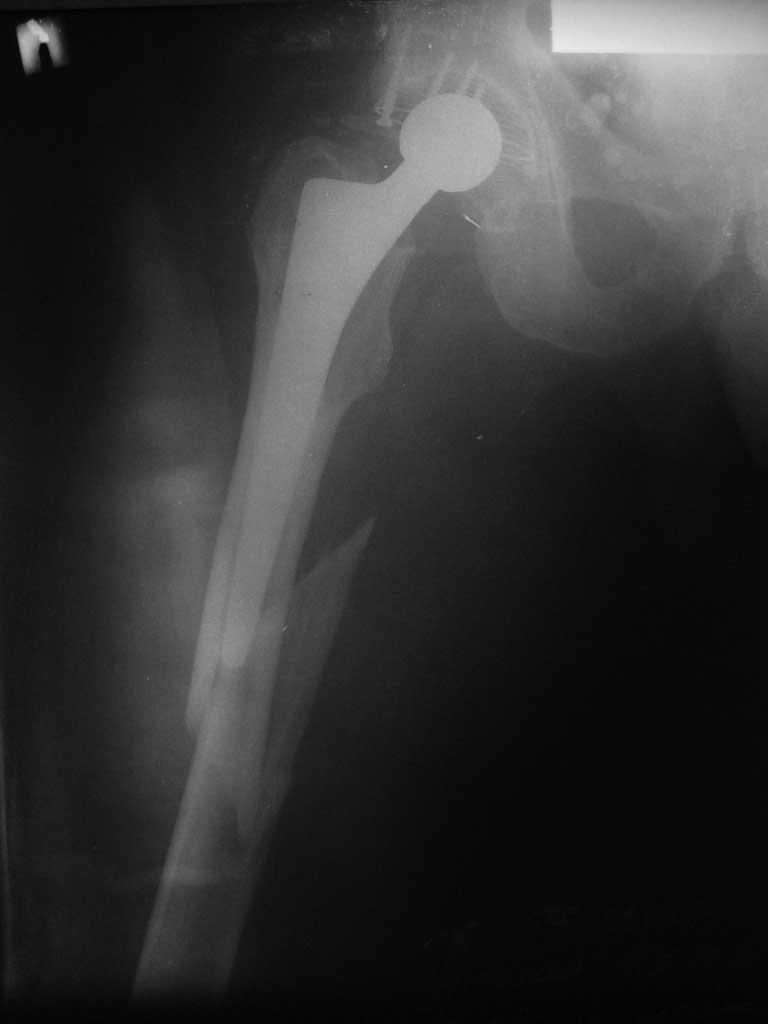

Re: Перипротезный перелом

послал Михаил 30 Сентябрь 2011, 20:50